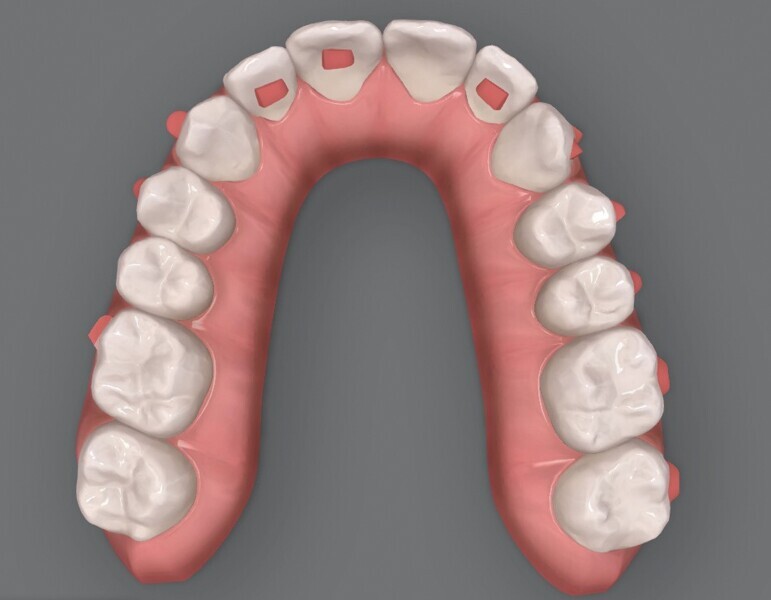

Le premier plan de traitement par simulation ClinCheck prévoit 53 aligneurs, afin de réaliser une distalisation séquentielle postérieure d’environ 4 mm sur le côté gauche du maxillaire, une expansion de 2 mm par quadrant et un alignement dans la zone antérieure. Il prévoit également une réduction interproximale (RIP) sélective de 0,25 mm sur chaque face des dents de l’arcade mandibulaire, et de 0,10 mm à 0,15 mm pour les dents de l’hémiarcade maxillaire droite (Fig. 4). Une application topique de fluorure est planifiée dans les zones soumises à une RIP après la procédure. Des élastiques de classe II sont utilisés du côté gauche pour faciliter la distalisation. La fréquence de changement des aligneurs est fixée à sept jours et elle sera ramenée à cinq jours par la suite. Un accélérateur de traitement orthodontique par vibrations est utilisé, afin d’augmenter la vitesse et la prédictibilité des mouvements dentaires. Le traitement n’envisage pas l’utilisation d’aligneurs de surcorrection.

Fig. 5a : Plan supplémentaire du traitement par aligneurs conçu par ClinCheck (début).

Fig. 5b : Plan supplémentaire du traitement par aligneurs conçu par ClinCheck (début).

Fig. 5c : Plan supplémentaire du traitement par aligneurs conçu par ClinCheck (début).

Figs. 5d : Plan supplémentaire du traitement par aligneurs conçu par ClinCheck (début).

Fig. 5e : Plan supplémentaire du traitement par aligneurs conçu par ClinCheck (début).